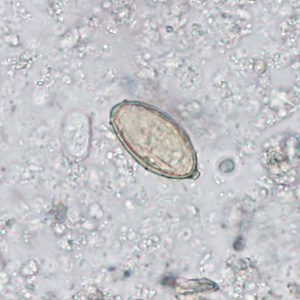

DPDx is an educational resource designed for health professionals and laboratory scientists. For an overview including prevention, control, and treatment visit www.cdc.gov/parasites/.